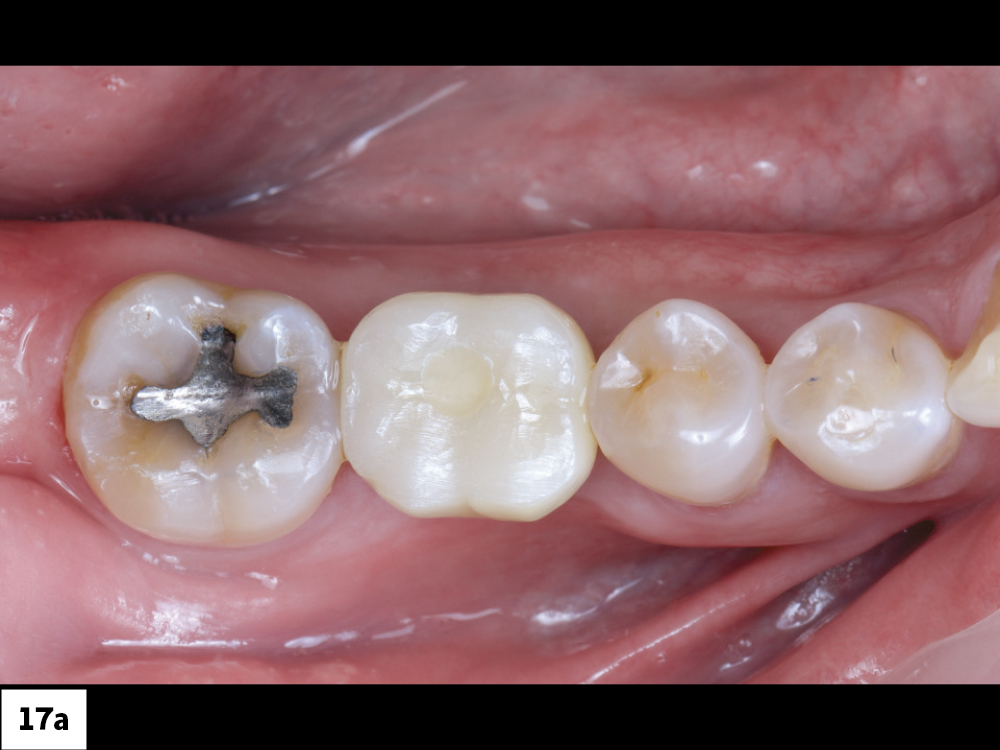

Figures 17a, 17b: The final BruxZir Esthetic screw-retained crown was fabricated by Glidewell. After it was seated, the access channel was filled with Teflon tape and sealed with composite.